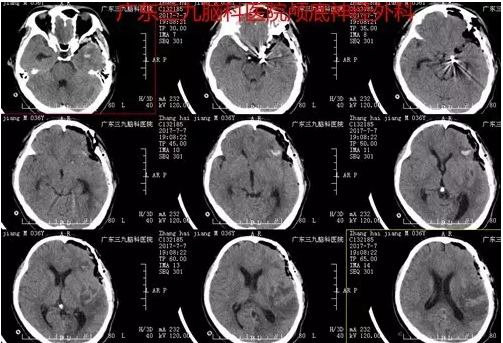

图7:动脉瘤夹闭术后造影提示动脉瘤已不显影,血流通畅,动脉瘤夹在位

图8:术后CT提示术后改变